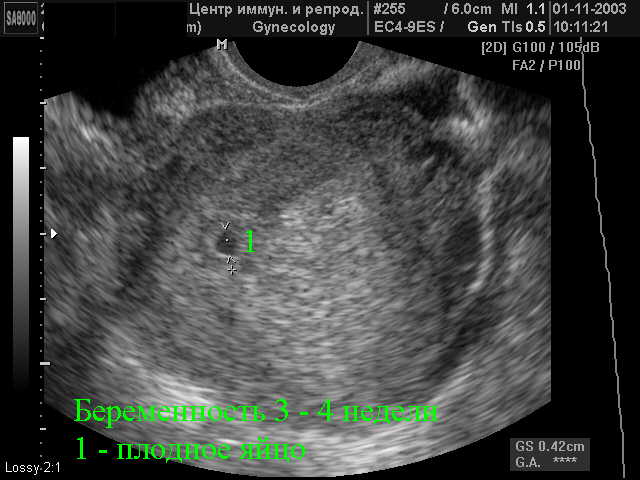

Записали на узи через 3 недели . . . . .эмбриометрия соответствует 5,4 недели .Не исключена монозиготная двойня . Видно по фото 2 желточных мешочка один 3,6 второй 2,2 .сердечко слышно одно, написали . . .

Если результаты анализов и УЗИ не совпадают, то женщине назначают повторное обследование через 2-3 недели . Если двойня обнаружена на сроке в 5 недель, то врач может сообщить об этом не сразу . . .

3 Как выглядит двойня на УЗИ? 4 В каких случаях можно не увидеть двойню? . . . Чтобы определить количество плодов на УЗИ 5-й недели, смотрят на следующие признаки: